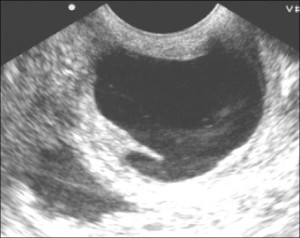

Но как диагностируется киста шейки матки? Очень легко определить данное заболевание во время колькоскопии или при УЗИ с применением влагалищного датчика. Иногда болезнь можно обнаружить визуальными методами, например, перед менструацией образование увеличивается в размерах, начинает кровоточить, приобретает синюшный оттенок, принимает эндометриозную форму.